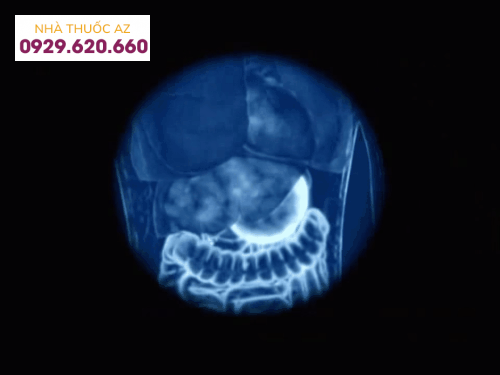

Hệ thống tiêu hóa của bạn được tạo thành từ năm phần chính:

Miệng

Thực quản

Dạ dày

Ruột non

Ruột già